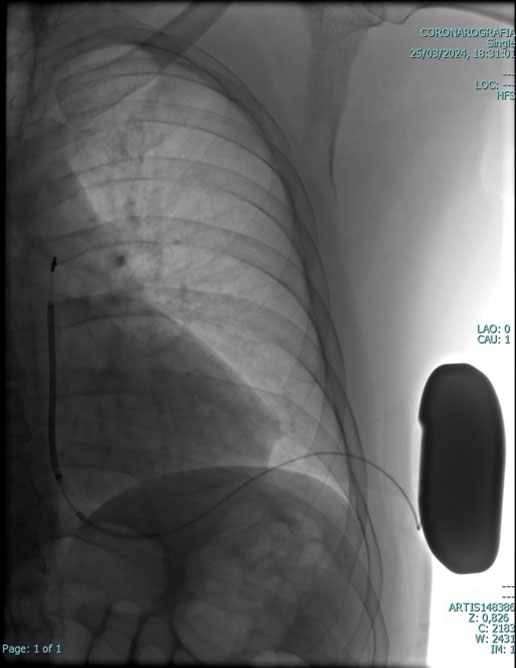

Gli impulsi elettrici trasmessi dal Pace Maker al cuore sono di bassissima intensità e non vengono assolutamente avvertiti dal paziente. Il Pace Maker viene inserito mediante una semplice procedura: in anestesia locale si pratica una piccola incisione della pelle, di pochi centimetri, nella regione alta del torace, sotto la clavicola sinistra. Si cerca quindi una vena per l'introduzione dei cateteri, che vengono guidati fino al cuore, controllandone il percorso mediante la radioscopia; dopo aver controllato che i parametri elettrici siano regolari, i cateteri vengono collegati al Pace Maker che viene infine inserito in una piccola tasca sotto la pelle; tutto ciò avviene in modo del tutto indolore.

PACE MAKER LEADLESS

L'evoluzione della ricerca e conseguenzialmente della tecnologia in particolare in campo cardiologico, ha consentito di sviluppare sistemi di stimolazione cardiaca miniaturizzati e “senza fili” (“leadless pacemaker”), in cui il generatore d'impulsi e gli elettrodi sono contenuti in una singola unità totalmente intracardiaca, eliminando quindi la presenza degli elettrocateteri convenzionali e della tasca pre-pettorale sottocutanea.

La terapia con pacemaker (PM) senza elettrocateteri (“leadless”) rappresenta una realtà nel campo dell'elettrostimolazione cardiaca. I PM leadless hanno come obiettivo primario quello di ridurre le complicanze legate all'introduzione di elettrocateteri endocavitari e alla creazione della “tasca sottocutanea” in regione sottoclaveare, e si propongono come valida alternativa nei pazienti con controindicazioni alla stimolazione cardiaca tradizionale. I vantaggi dei pacemaker leadless sono legati essenzialmente alle loro piccole dimensioni, al minimo peso, all'assenza di meccanismi di connessione tra generatore ed elettrodi, dato che questi coesistono in una singola unità, alla procedura di impianto mini-invasiva transcatetere, e al considerevole minor rischio di infezioni.

Pace maker leadless cardiologia Vallo della Lucania Pace maker leadless cardiologia Vallo della Lucania

I pacemaker leadless possono essere posizionati nella cavità ventricolare ed eventualmente, atriale destra con una procedura mini invasiva per via transcatetere con approccio transcutaneo utilizzando la vena femorale (dall'inguine), attraverso uno speciale introduttore. Il sistema non richiede quindi la creazione di una tasca e non lascia cicatrici esterne visibili.

Questo nuovo tipo di Pacemaker è totalmente intracardiaco è formato da un dispositivo fissato direttamente all'interno del ventricolo destro, ed eventualmente atrio destro. Nel caso di un impianto bicamerale (atrio e ventricolo destro), grazie ad un innovativo sistema di comunicazione, i device riescono a “parlare“ tra di loro per sincronizzare le due camere cardiache. L'introduzione di questo tipo di tecnologia  leadless da inizio ad una nuova era del pacing intracardiaco.